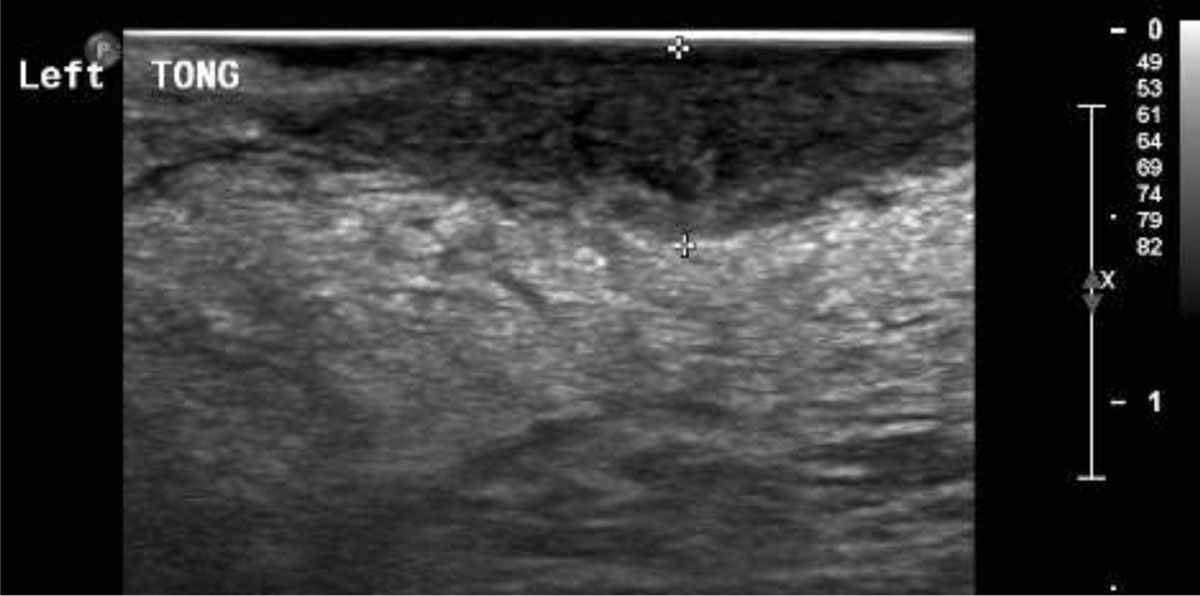

Figure 2

Patient with squamous cell carcinoma of the tongue. Intraoral ultrasound image showing the hypoechoic tongue tumor infiltrating the normal (echogenic) tongue musculature. The distance between the two calipers indicates the depth of invasion (DOI).